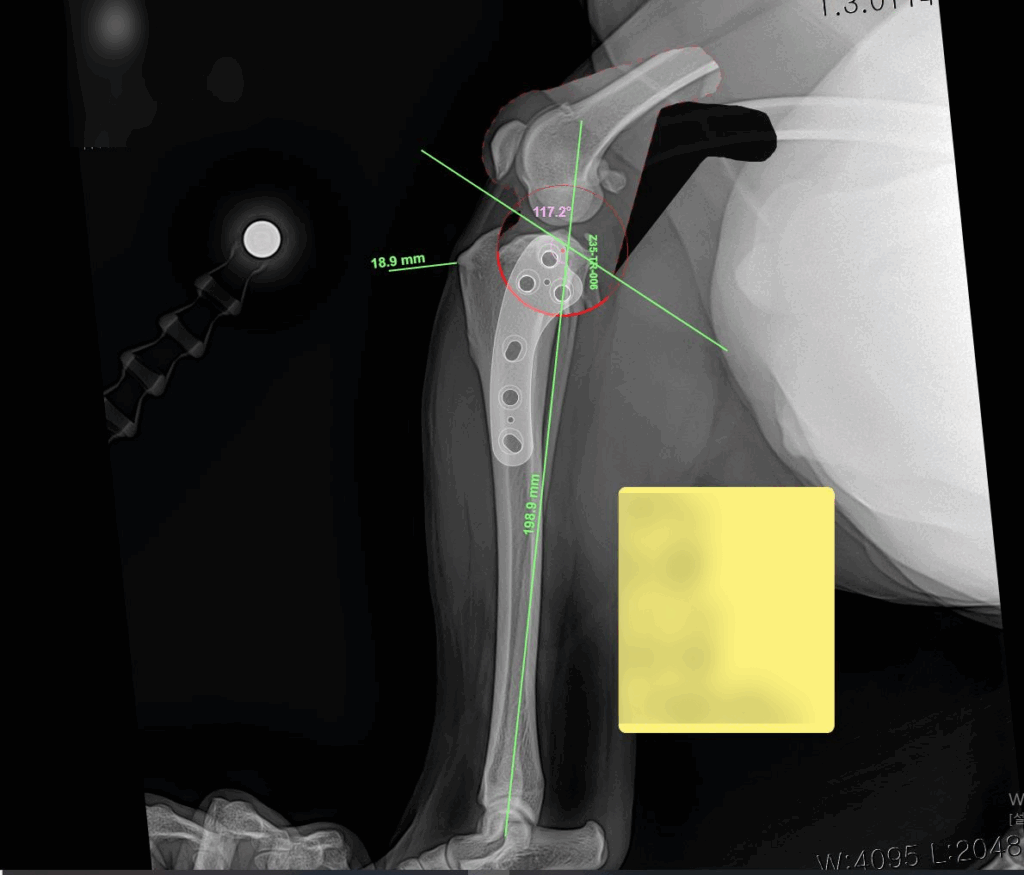

라온동물메디컬센터에서는 동물 정형외과 전용 전문 프로그램을 활용하여 수술 전 정밀 시뮬레이션을 선행한 뒤 진행되었습니다. 개별 환자의 뼈 구조와 각도, 절골 범위를 사전에 계산함으로써 수술 정확도는 물론, 회복 안정성까지 높일 수 있었습니다.

수술 시뮬레이션 사진 / 출처: 라온동물메디컬센터